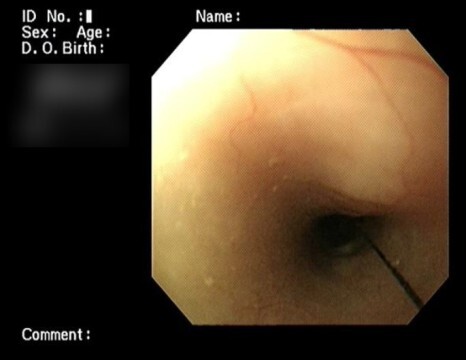

내시경 검사에서 식도부터 위까지

위에서도 십이지장까지 끈이 지나가는 것을

확인할 수 있었습니다.

위부터 소장까지 걸려있는 것은 확인하였으나

식도 쪽 말단 부를 확인할 수 없어서

구강을 다시 확인하였습니다.

혀 밑에 두 가닥의 실로 묶여 있는 것을 확인할

수 있었습니다.